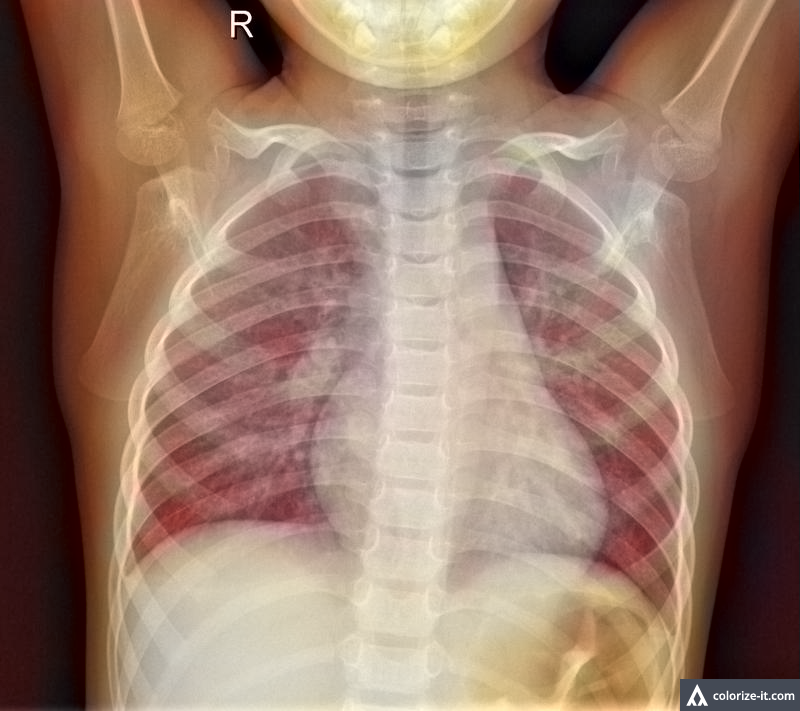

The third technique was the expansion of the color scheme. On the execution side of this technique, the average R, G and B values are found among the images. Then, all the respective RGB values are multiplied with the mentioned average value for expanding, increasing the overall values and yielding a colorized version of the image. This technique was used in order to make the features clearer while classifying the image. A sample of the colorized version can be found in fig 5.

Refer to caption

Figure 5: X-ray Image with Expanded Color Scheme